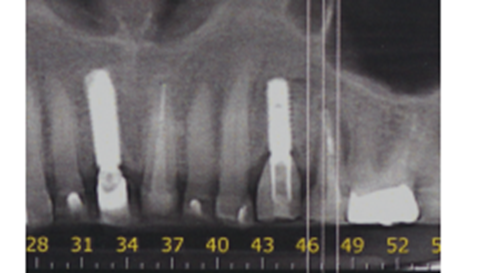

Paciente do sexo feminino, com viagem marcada para o exterior, apresentou-se em minha clínica com o diagnóstico de lesão e grande mobilidade do elemento 25. Após a solicitação dos exames preliminares e da anamnese, foi realizada a conduta medicamentosa e a cirurgia foi marcada para instalação imediata do implante (Figuras 3 e 4).

Foi eleito um implante Veloce Cone Morse de 3.75 X 11.5 mm e após a exodontia, o implante foi instalado utilizando o protocolo de fresagem recomendado pelo fabricante, fazendo uso das fresas escalonadas do sistema, alcançando um torque de inserção de 70 Ncm, o que me incentivou a promover o carregamento imediato deste implante (Figuras 5, 6, 7, 8, 9 e 10).